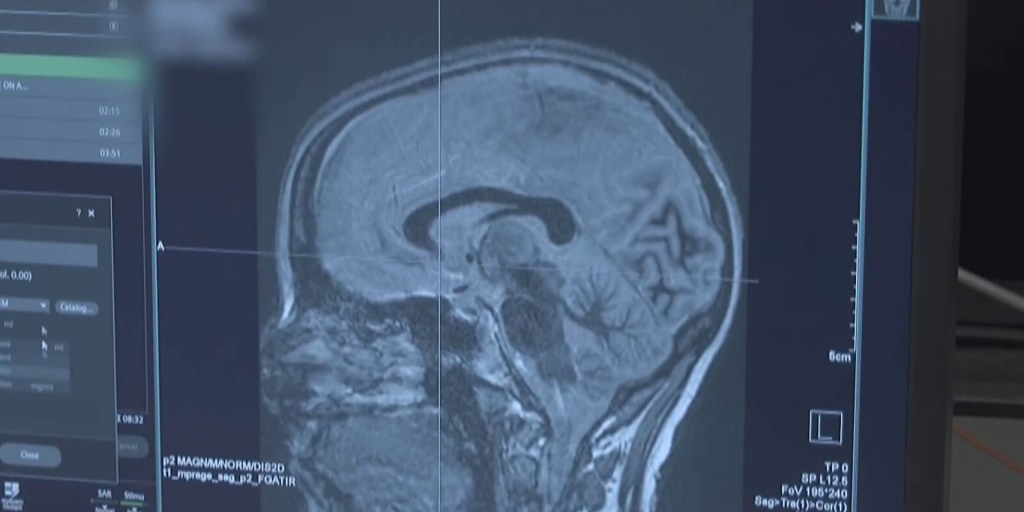

New technology offers hope for Parkinson’s patients A new technology is giv...